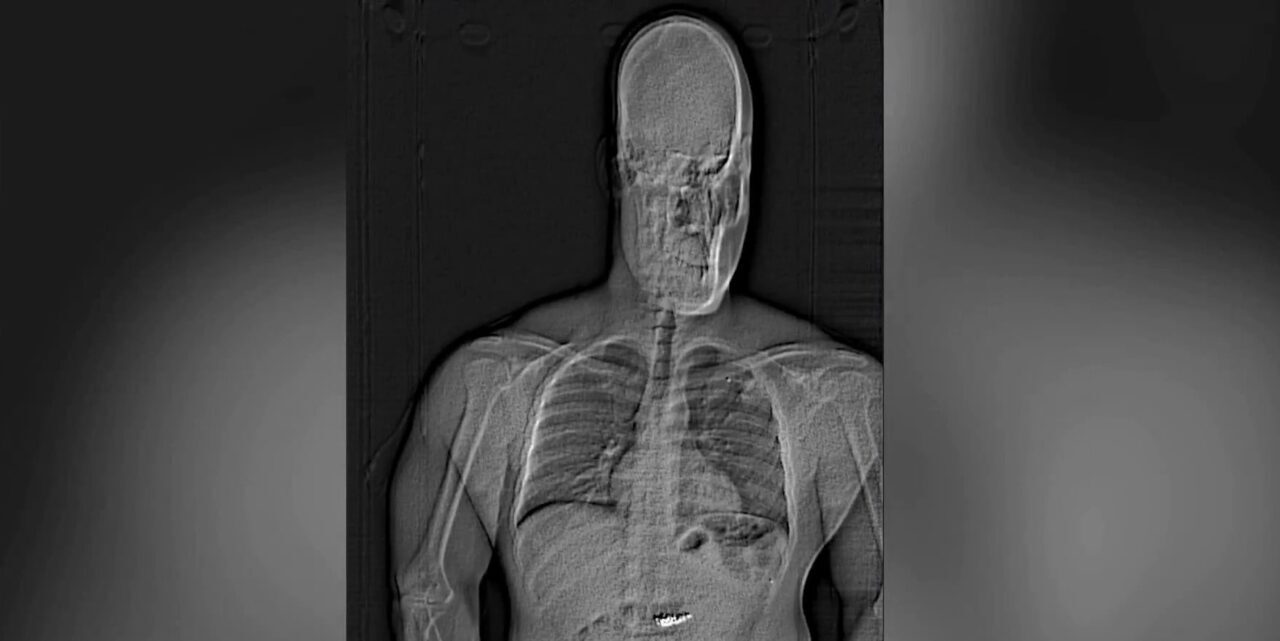

Orlando Polis Departmanı’nın sosyal medya hesabından yapılan açıklamada, 26 Şubat’ta ünlü bir mücevher mağazasında hırsızlık yapıldığı belirtildi. Açıklamada, Jaythan Gilder isimli hırsızın, girdiği mücevher mağazasındaki özel koleksiyon takıları görebilmek için Amerikan Basketbol Ligi’nde (NBA) oynayan bir basketbolcunun asistanı gibi davrandığı ve daha sonra görevlilerin dikkatini dağıtarak yaklaşık 769 bin dolarlık küpeler ile 575 bin dolarlık bir yüzükle kaçtığı kaydedildi. Gilder’ın kısa süre sonra yakalandığı ve röntgen muayenesinde çaldığı küpelerin midesinde olduğunun belirlendiği aktarıldı.

Açıklamada, günlerce hastanede gözetim altında tutulan hırsızın vücudundan küpelerin doğal yollarla çıkarıldığı ve yetkililer tarafından teyit edildikten sonra mağazaya teslim edildiği bilgisi paylaşıldı.